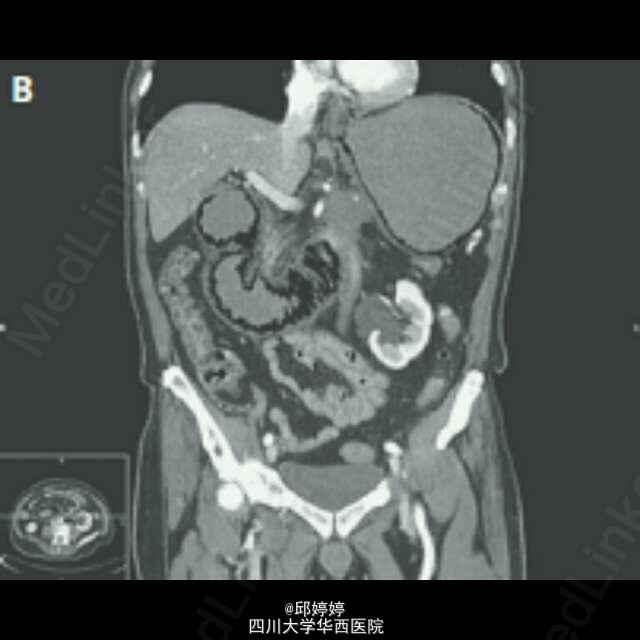

灾难性胃肠积气

患者,老年男性,胰腺癌晚期,腹痛,呕吐12h,触诊腹部压痛,板状腹。平片(图1)示腹腔严重积气,CT(图2-3)示胃肠周围,门静脉积气。患者拒绝治疗,48h后死亡。